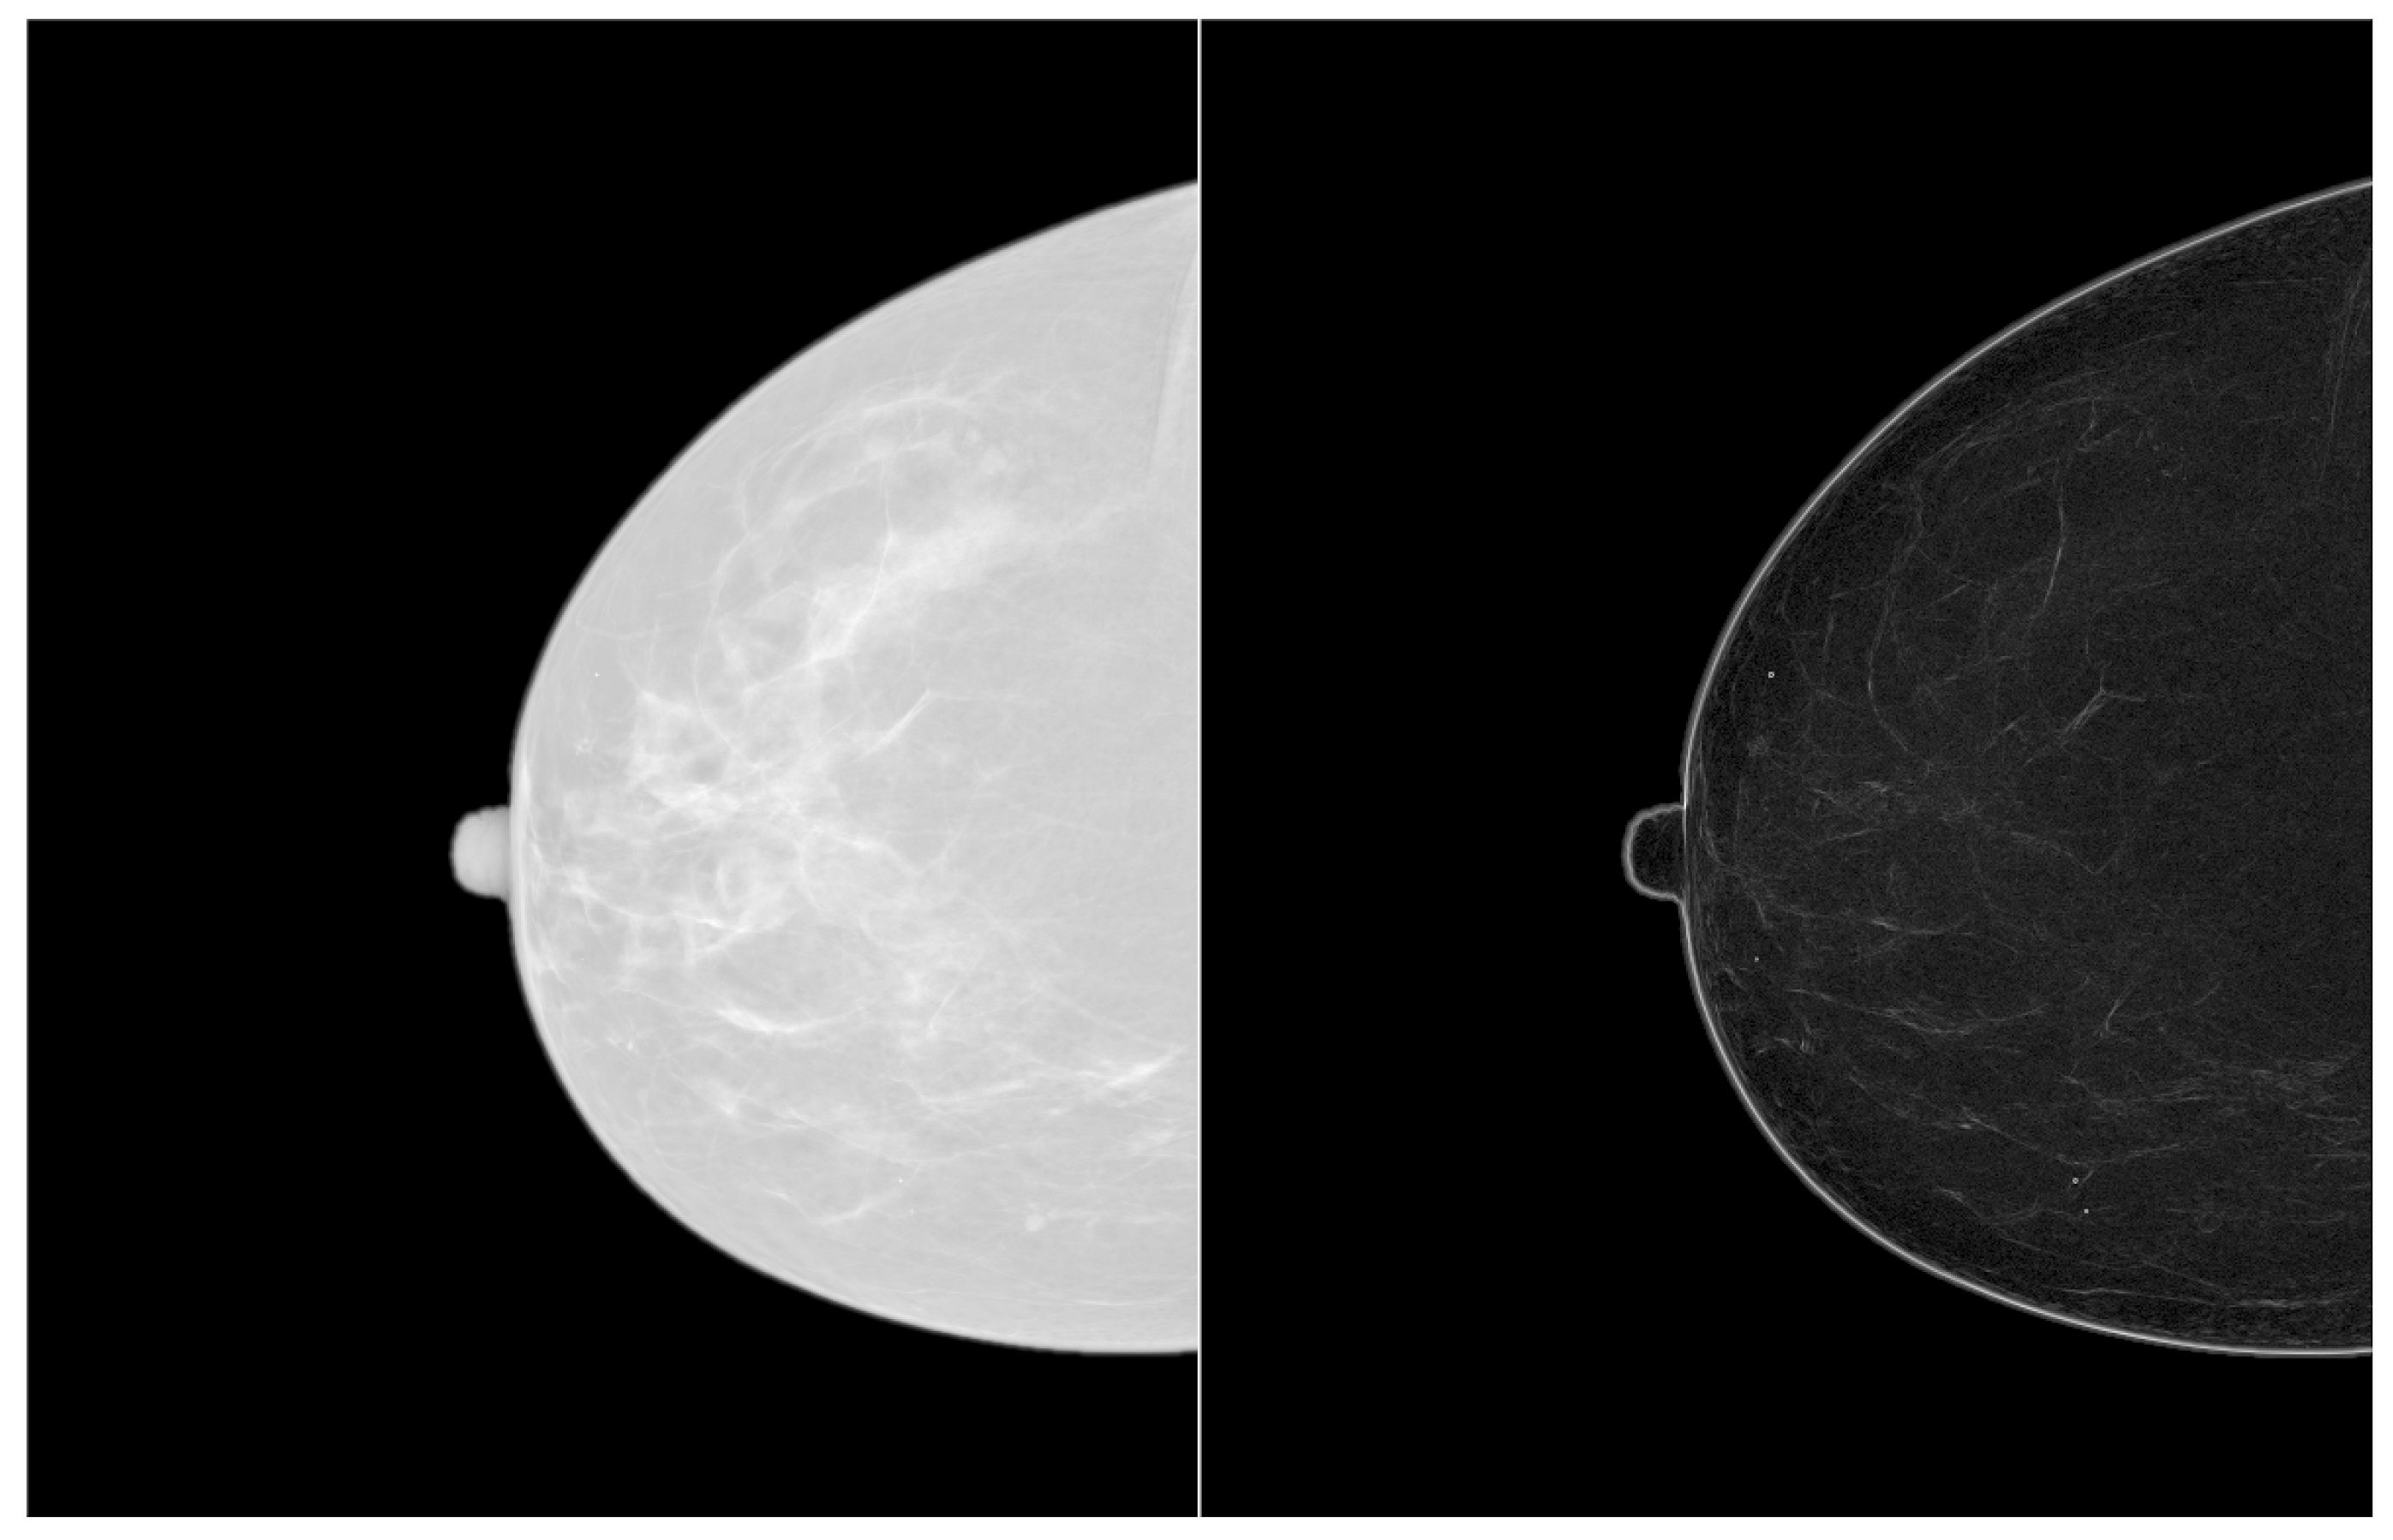

Filtering of Mammograms Based on Convolution with Directional Fractal Masks to Enhance Microcalcifications

Abstract